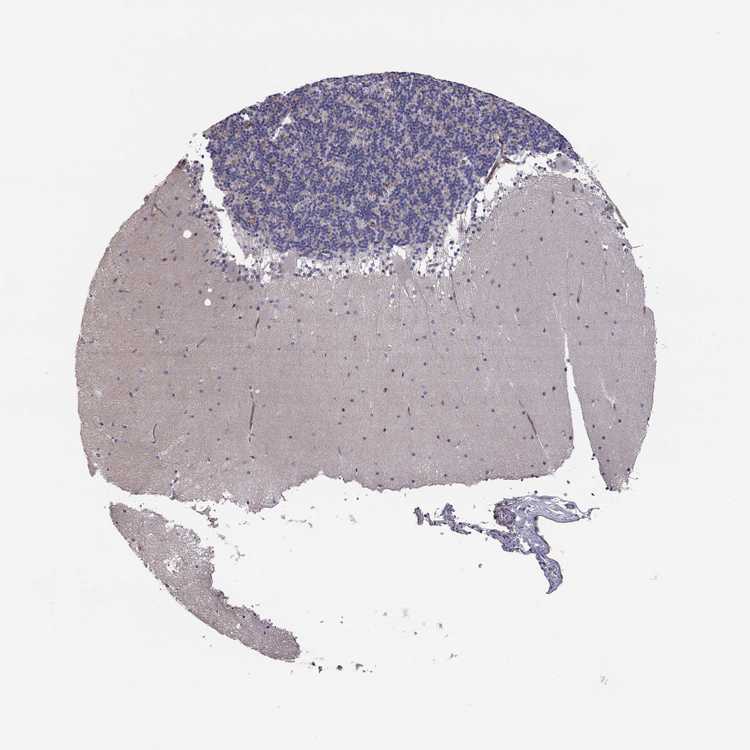

BRAIN CEREBELLUM Show tissue menu

CEREBELLUM - Antibody stainingi

Antibody staining in the annotated cell types in the current human tissue is reported as not detected, low, medium, or high, based on conventional immunohistochemistry profiling in selected tissues. This score is based on the combination of the staining intensity and fraction of stained cells.

Each image is clickable and will lead to virtual microscopy that enables deeper exploration of all samples and also displays staining intensity scores, fraction scores and subcellular localization as well as patient and tissue information for each sample.

Antibody HPA073904

Purkinje cells Not detected

Cells in granular layer Low

Cells in molecular layer Not detected